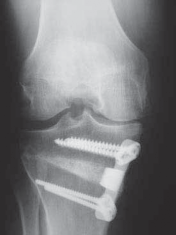

A C B D TECH FIG 7•A.

B.

Intraoperative final AP radiograph.

C,D.

Postoperative AP and lateral radiographs.